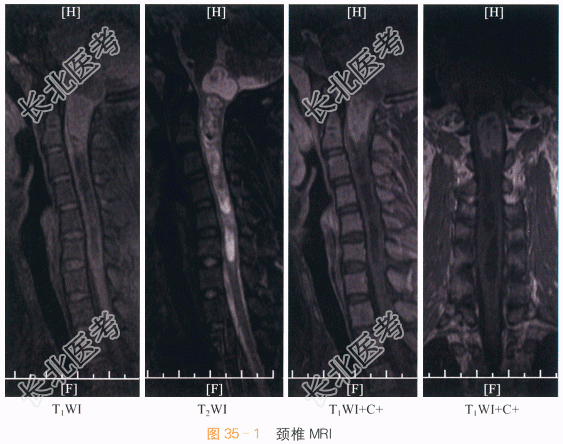

影像学资料如图35-1所示。

读片分析:颈椎矢状面、冠状面MR成像示C₁~C₂水平髓内病变:T₁加权像上等于脊髓信号,T₂加权像上,病变信号略高于脊髓,病变由许多微囊组成,病变下缘T₁WI、T₂WI均见含铁血黄素沉着线样低信号,肿瘤头、尾端见明显长T₁、T₂囊腔,远端脊髓中央管扩张,病变两侧蛛网膜下腔变窄。增强后MRI检查显示病变呈明显不均匀强化,其边界显示清晰、锐利,肿瘤内囊变、坏死部分及肿瘤头、尾端囊腔、脊髓空洞无强化。